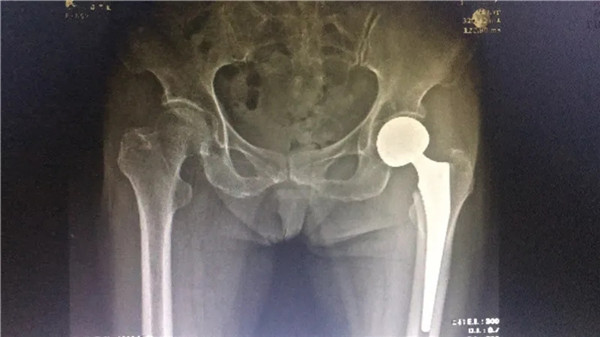

術(shù)后

6月4日,在完善各項(xiàng)術(shù)前檢查,身體狀況符合手術(shù)指征后,陳阿婆接受了左髖關(guān)節(jié)置換術(shù)。手術(shù)由危立軍副院長主刀,一個(gè)半小時(shí)后,手術(shù)圓滿成功。術(shù)后,陳阿婆恢復(fù)良好,一周后,便可以下地行走。術(shù)后半個(gè)月,陳阿婆出院回家休養(yǎng)。